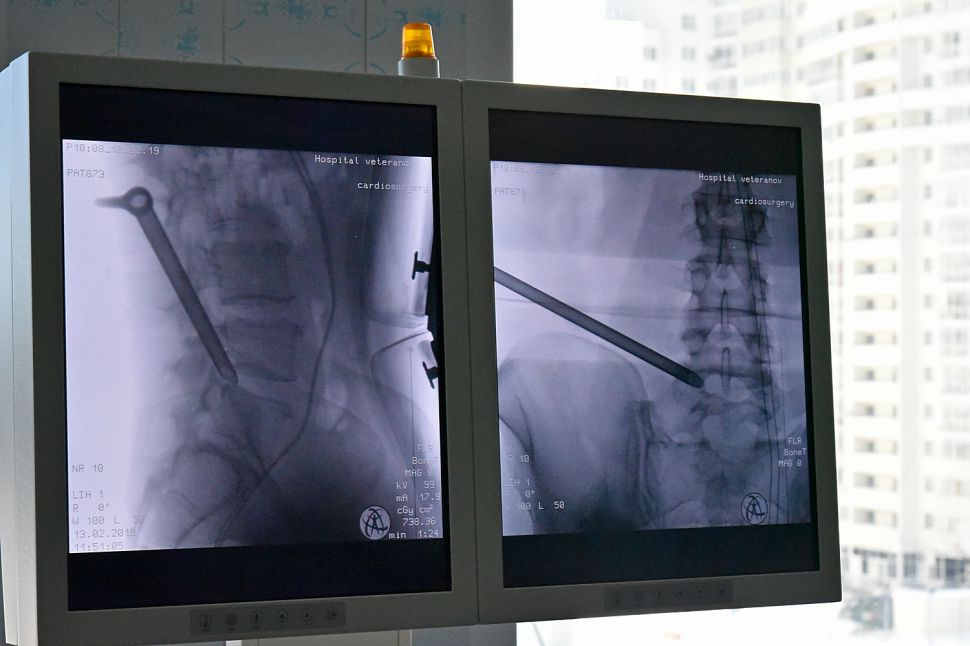

Сегодня в Екатеринбурге состоялась презентация новой для здравоохранения региона методики – эндоскопическая операция при заболеваниях позвоночника.

По словам Бориса Сыченикова, эндоскопическое удаление считается самым щадящим методом операционного лечения позвоночных грыж, так как операция выполняется не через разрез, а через прокол брюшной полости, диаметр которого не превышает 7 мм. Туда вводятся специальные инструменты. Это позволяет не только избежать травмирования мышц и связок, но и уменьшить интенсивность постоперационных болей. Почти 70% пациентов, перенесших удаление межпозвоночной грыжи при помощи эндоскопа, говорят о том, что боли после операции длились не более 2-3 дней, а их интенсивность была вполне умеренной.

Еще одним важным моментом является возможность полного визуального контроля, для которого применяется специальная эндоскопическая установка с многократным увеличением. Такая техника позволяет максимально снизить возможные риски, связанные с повреждением спинномозговых корешков.

Сегодня Борис Сычеников провел две показательные операции в госпитали для ветеранов войн. Отметим, подобные хирургические вмешательства проводятся в Москве и ряде других российских городов. Для проведения эндоскопических операций требуется специальное медицинское оборудование немецкого производства.